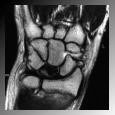

Figura 5: enfermedad de Kienböck en estadio precoz (en la RNM el semilunar se ve de color negro)

La resonancia nuclear magnética (RNM) es la prueba diagnóstica más útil porque permite el diagnóstico precoz de la enfermedad de Kienböck y evalúa los resultados tras la cirugía (figura 5). La tomografía axial computarizada (TAC) permite valorar mejor la estructura ósea y un estadiaje más preciso.

I: morfología y densidad radiológica del semilunar normal. En RNM sí se aprecia sí se aprecia de distinta condensación debido a la falta de sangre (figura 5).